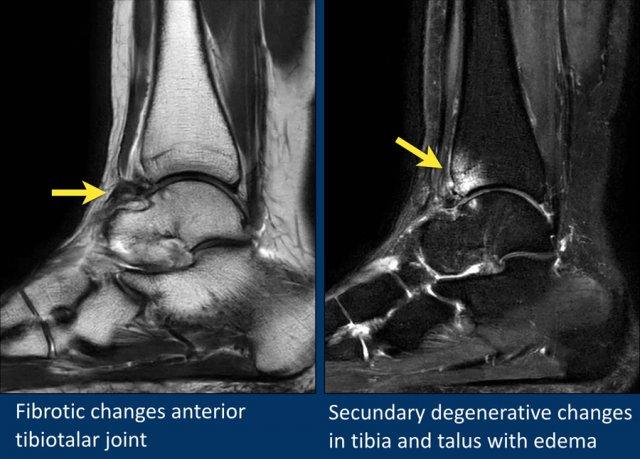

Giải phẫu trên mặt phẳng cắt ngang

Cuộn qua bộ ảnh để xem giải phẫu hệ thống dây chằng trên mặt phẳng cắt ngang.

Bạn có thể nhấp vào ảnh để phóng to.

Các khớp chày mác (syndesmosis) được quan sát rõ nhất trên ảnh cắt ngang:

- Dây chằng chày mác trước (anterior tibiofibular ligament) hay còn gọi là khớp chày mác trước (anterior syndesmosis)

- Dây chằng chày mác sau (posterior tibiofibular ligament) hay còn gọi là khớp chày mác sau (posterior syndesmosis)

- Màng gian cốt (membrana interossei), chạy suốt lên đến chỏm xương mác.